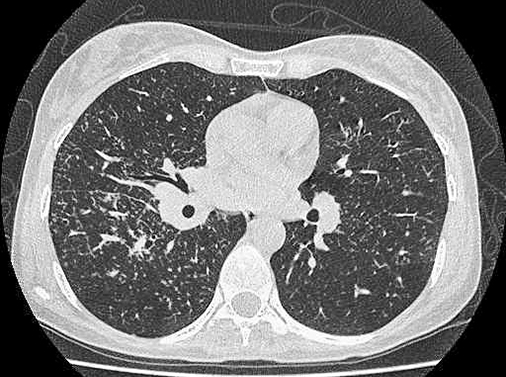

Ключевым для корректной диагностики является выполнение компьютерной томографии органов грудной клетки с целью оценки объема поражения и гистологической верификации. КТ высокого разрешения помогает оценить изменения вокруг бронхов, а в интерстиции — очаги, расположенные вдоль сосудисто-бронхиальных тяжей и под плеврой. Мелким очагам может сопутствовать «матовое стекло». У 1/3 пациентов выявляются нетипичные изменения: большие тени (диаметром 2–4 см) или узловатые изменения с наличием увеличенных лимфоузлов (см. рис. 3).

Рис. 3. КТ-картина интерстициально-узелковых изменений в легких, увеличение внутригрудных лимфатических узлов, характерное для саркоидоза.